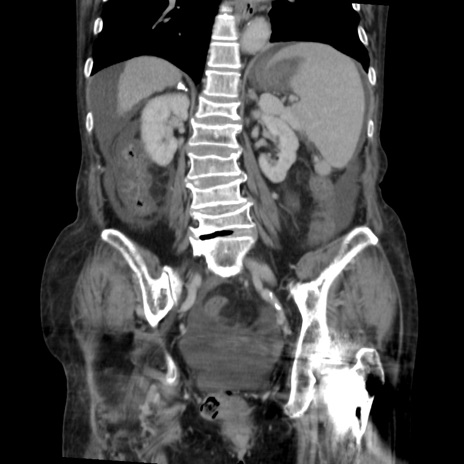

症例31(冠状断像)

【症例】80歳代 女性

【主訴】腹部膨満感

【現病歴】他院にて肝硬変にてフォロー中。1週間前から便秘、腹部膨満感、臍部腫瘤あり受診となる。

【既往歴】肝硬変

【身体所見】腹部膨隆あり、皮膚変化なし、疼痛なし。